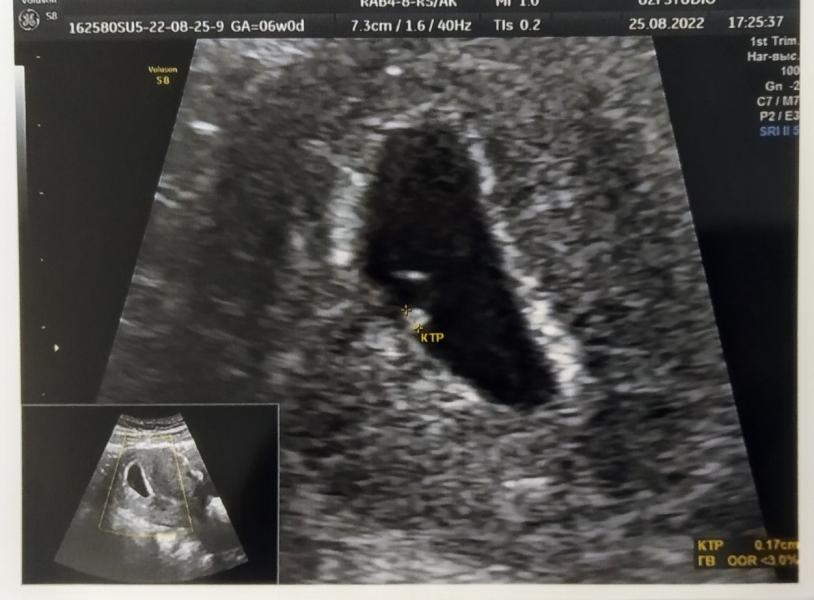

У нас все хорошо. Срок почти совпадает, по мес 6 недель, по УЗИ 5-6 недель. ПЯ - 20 мм, КТР - 1,7 мм. ❤️Сердечко видно, но еще не слышно, тк ещё совсем крошка.

И да, малыш один😁😁